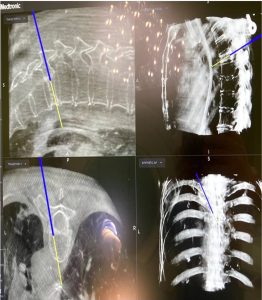

Εικόνα 9 (α,β,γ,δ) : Προεγχειρητική Μαγνητική Τομογραφία, πλαγία λήψη (α) ακολουθία Τ2. Παρατηρείται καταστροφή του θωρακικού σπονδύλου, λόγω μετάστασης από τον προστάτη και πίεση του νωτιαίου μυελού από νεοπλασματικές μάζες. Ο ασθενής υποβλήθηκε σε χειρουργική επέμβαση συνιστάμενη σε ανοικτή αποσυμπίεση του νωτιαίου μυελού από τις νεοπλασματικές μάζες και σε σταθεροποίηση της Σπονδυλικής Στήλης δια διαδερμικής σπονδυλοδεσίας (β,γ,δ).